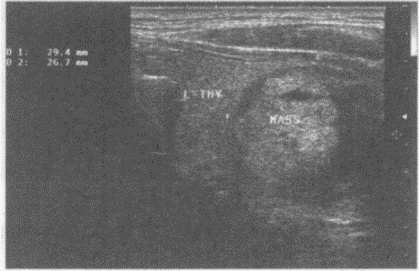

临床资料:女,45岁,自述发现左颈部包块1年余。超声综合描述:甲状腺右叶形态大小正常,内可见数个低回声区(箭头所示),无包膜,内回声尚均匀;左叶增大失常态,内可见6.9cm×4.0cm中等回声,边界清晰,内回声不均,中部可见3.5cm×1.8cm不规则无回声区,CDFI:双侧甲状腺内血流信号不丰富,低回声区内可见少许血流信号。

超声提示()。

A.甲状腺腺瘤

B.毒性甲状腺肿(原发性甲状腺功能亢进)

C.结节性甲状腺肿并囊性变

D.甲状腺正常声像图